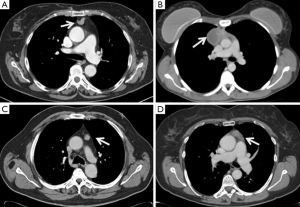

We reviewed the data of 134 patients undergoing robotic thymectomy for clinically defined early-stage thymoma (Masaoka stages I and II) collected between 2002 and 2014 by four European Thoracic Surgery Centres (University of Maastricht-Nederland; University of Padova-Italy; University of Pisa-Italy; University of Innsbruck-Austria). All patients signed a detailed consent form in which they were informed about possible complications of a thymoma resection with robotic approach and the lack of long-term data. The institutional review board of each centre approved the study. Information on patient demographics, presence of associated MG, tumor characteristics, stage, intra and postoperative data (e.g., complications, need for open conversion or additional ports or accesses, operative time, length of hospital stay) were collected. The Masaoka staging system was used to assess the pathological stage (2), while the new World Health Organization classification was used for histological definition (13). The Myasthenia Gravis Foundation of America (MGFA) classification (14) was applied to stratify the preoperative class of MG. Preoperative assessments included evaluation of pulmonary and cardiac functions, total body computed tomography (CT) or magnetic resonance imaging (MRI). Preferred radiological characteristics to be eligible for robotic thymectomy were the location of the tumor in the anterior mediastinum, a distinct fat plane between the tumor and surrounding structures, unilateral tumor predominance, tumor encapsulation, existence of residual normal appearing thymic tissue, and no mass compression effect (Figure 1) (7). In cases of unexpected intraoperative finding of involvement of surrounding structures (Masaoka stage III), pleuro-pericardial or pulmonary nodules (Masaoka stage IVa/b), the robotic approach was converted to an open approach if the resection was considered technically difficult, unfeasible or unsafe for the patient. Patients were followed up until death or May 2015, if alive, by periodic visits (with neurologists if affected by MG) and phone contact. A total body computed tomography scan was performed every six months for the first two years postoperatively, then every year. There were 61 (45.5%) males and 73 (54.5%) females, with a median age of 59 years (range, 14–88 years). Seventy (52.2%) patients were affected by MG.

The side of surgical access was based on a single surgeon’s experience, or occasionally on the presence of unilateral tumor predominance. The surgical technique of robotic thymectomy from either the left or right side has been described in existing literature (15,16). This procedure was performed differently from thymectomy for non-thymomatous patients, with all surgeons adopting a “no-touch technique” for an “en bloc” resection of thymus and perithymic fat tissue. In this technique, the thymoma was never touched and the normal thymic tissue and peri-thymic fat were used for grasping and for traction. This technique avoids a direct manipulation of the tumor, in order to minimize the risk of tumor seeding in consequence of capsule damage. All thymus and perithymic fat were dissected with safe surgical margins, according to the International Thymic Malignancy Interest Group criteria (17), and the completeness of thymectomy was assessed by macroscopic inspection of the thymic bed, specimen and subsequent pathological analysis (Figure 2).